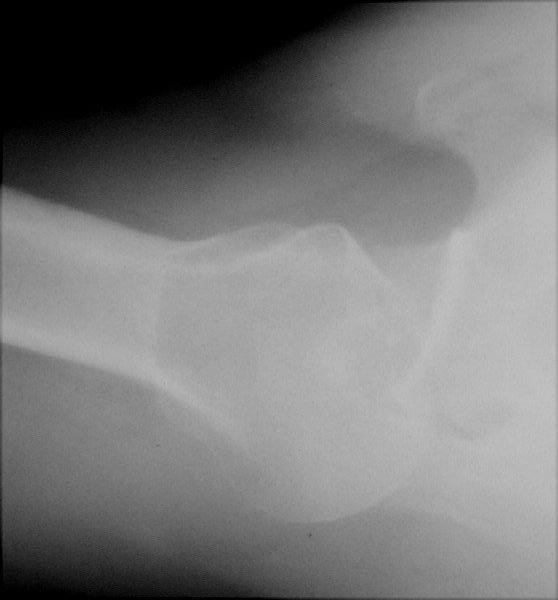

Return to Posterior Dislocation (Humerus)